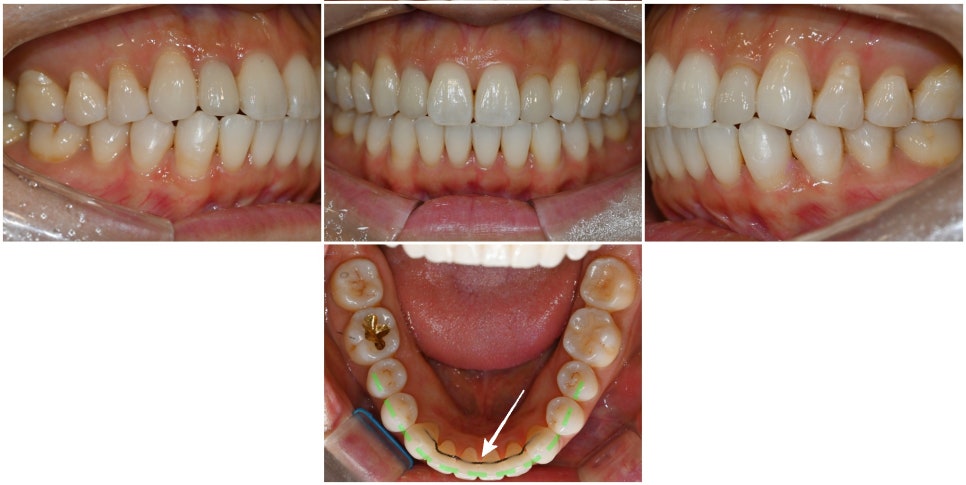

먼저 상악과 하악 교합면을 보겠습니다.

위쪽은 대체적으로 고르게 배열되어 있습니다.

그러나 아래 앞니를 보셨을 때,

다소 불규칙한 배열임을 알 수 있습니다.

다행스러웠던 부분은 심하게 틀어지지 않았기에

충분히 부분교정 방식으로 해결해볼 수 있습니다.

체크했을 때 어금니쪽은

배열이 좋고 잘 맞물리는 편입니다.

그러나 앞니는 절단면끼리 일자로

타이트하게 맞물리는 3급 부정교합인

절단교합 직전에 이르는 상태였습니다.

부분교정 치료가 끝나고 나서

가지런한 치열로 제자리를 찾아갔습니다.

이제는 어느 방향에서 보더라도

윗니가 아랫니를 살짝 덮고 있습니다.

원래 있어야 될 위치에 되돌려 놓으면서

치아 안쪽에는 재발 방지를 위한

얇은 철사(고정식 유지장치, fixed retainer)를

부착해뒀음을 확인할 수 있습니다.